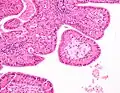

Low magnification micrograph of a Warthin tumor arising from the parotid gland. Low magnification micrograph of a Warthin tumor arising from the parotid gland.

The appearance of this tumor under the microscope is unique. There are cystic spaces surrounded by two uniform rows of oncocytes, which are epithelial cells with abundant, granular, eosinophilic cytoplasm.[7] The cystic spaces have epithelium referred to as papillary infoldings that protrude into them. Additionally, the epithelium has lymphoid stroma with germinal center formation.